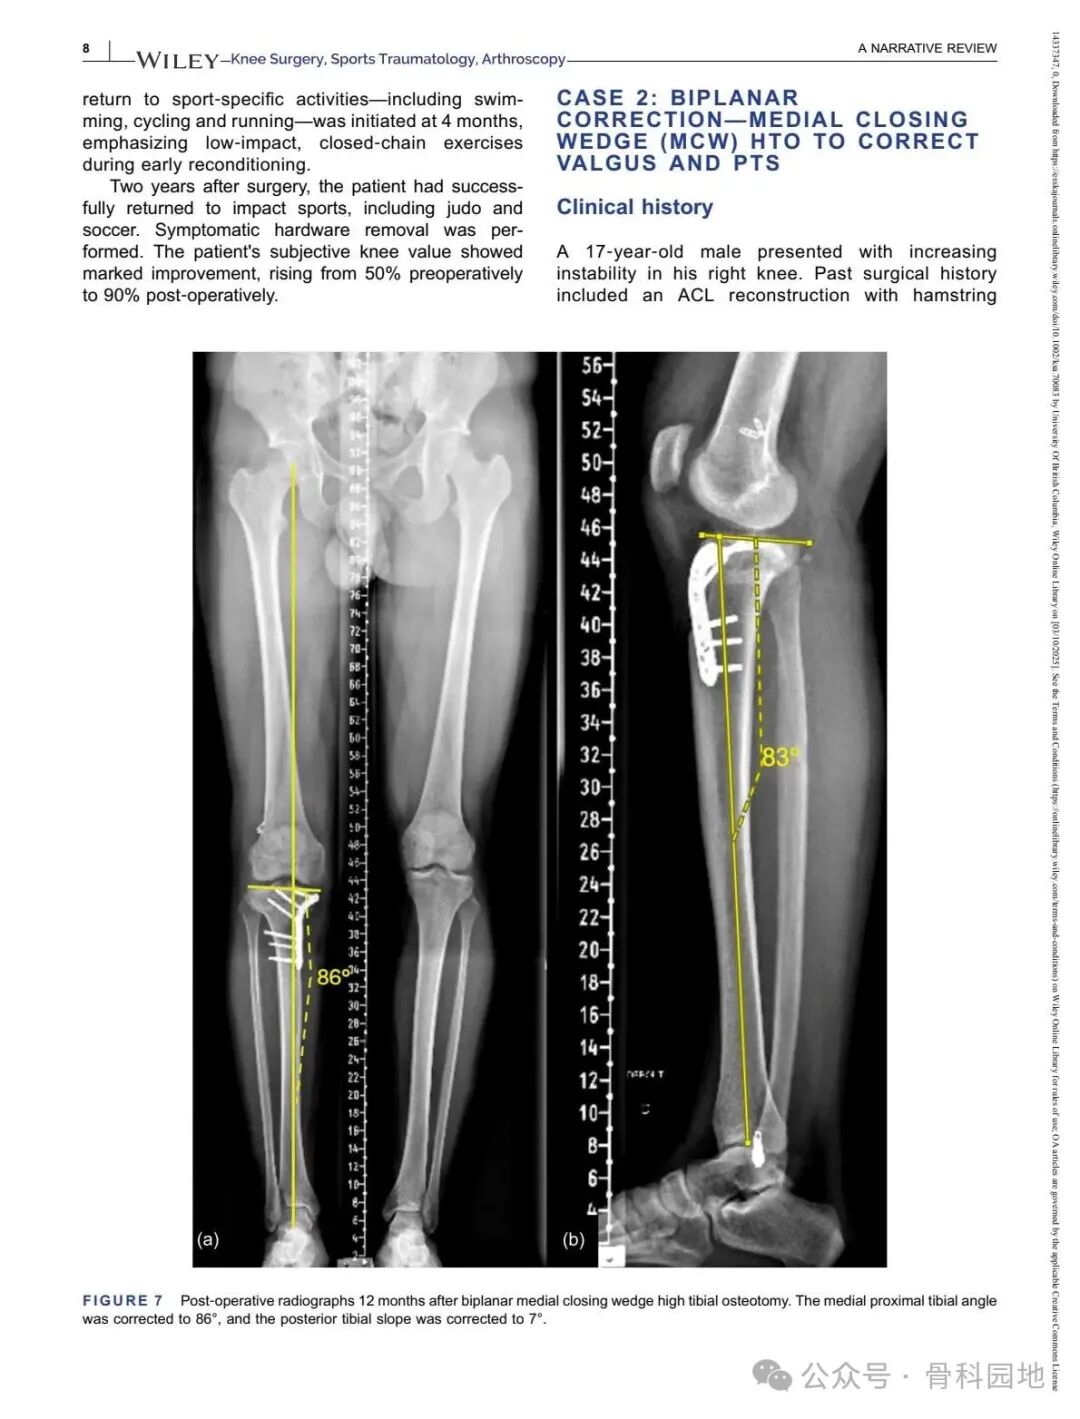

Although conventional high tibial osteotomy (HTO) primarily addresses coronal plane malalignment, the importance of sagittal plane alignment—specifically the posterior tibial slope (PTS)—cannot be overlooked in the setting of cruciate ligament insufficiency. Combined coronal and sagittal plane deformities are relatively rare and present unique surgical challenges. This narrative review summarizes the available literature and presents technical tips for managing complex biplanar deformities through a case‑based discussion of different techniques.